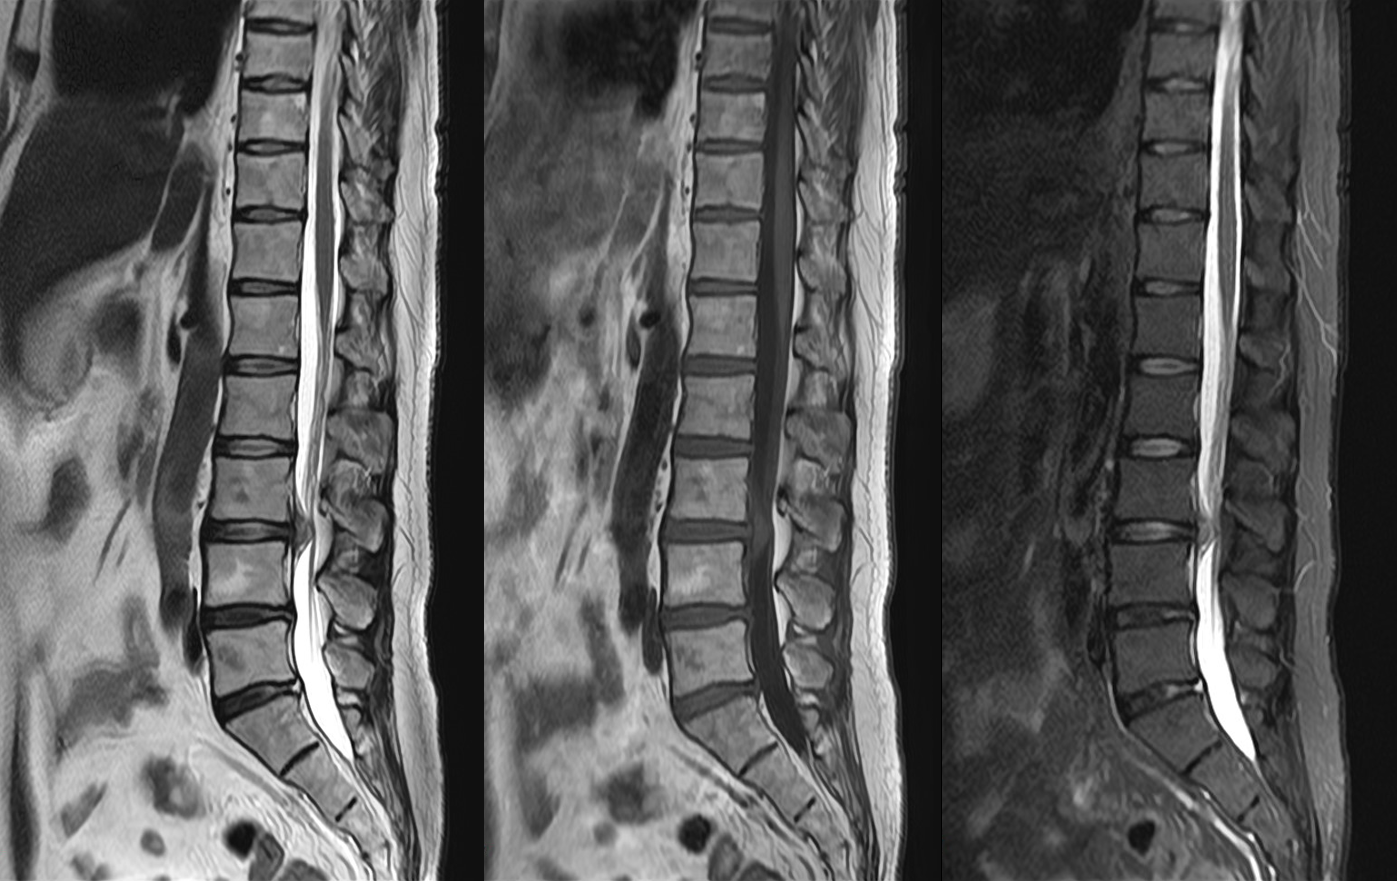

MRI

MRIとはMagnetic Resonance Imaging(磁気共鳴画像法)の略で、強力な磁石と電波を使って様々な角度から体の断面を画像化する検査です。

X線を使用しないため、放射線被ばくの心配がなく、軟部組織(筋肉、靱帯、神経など)の描出に優れており、がんの有無や広がり、転移の有無などを調べることができます。また、造影剤を用いずに血管を描出することが可能です。

部位や目的により異なりますが、検査時間は15分から40分程度です。複雑で高度な検査の場合は60分程かかる場合もあります。

当院ではCanon社製Vantage Fortian MRI 1.5Tを設置しており、主に脳血管疾患、脊椎疾患、閉塞性動脈硬化症などの下肢疾患、腹部疾患、心臓疾患、関節等の検査を行っています。